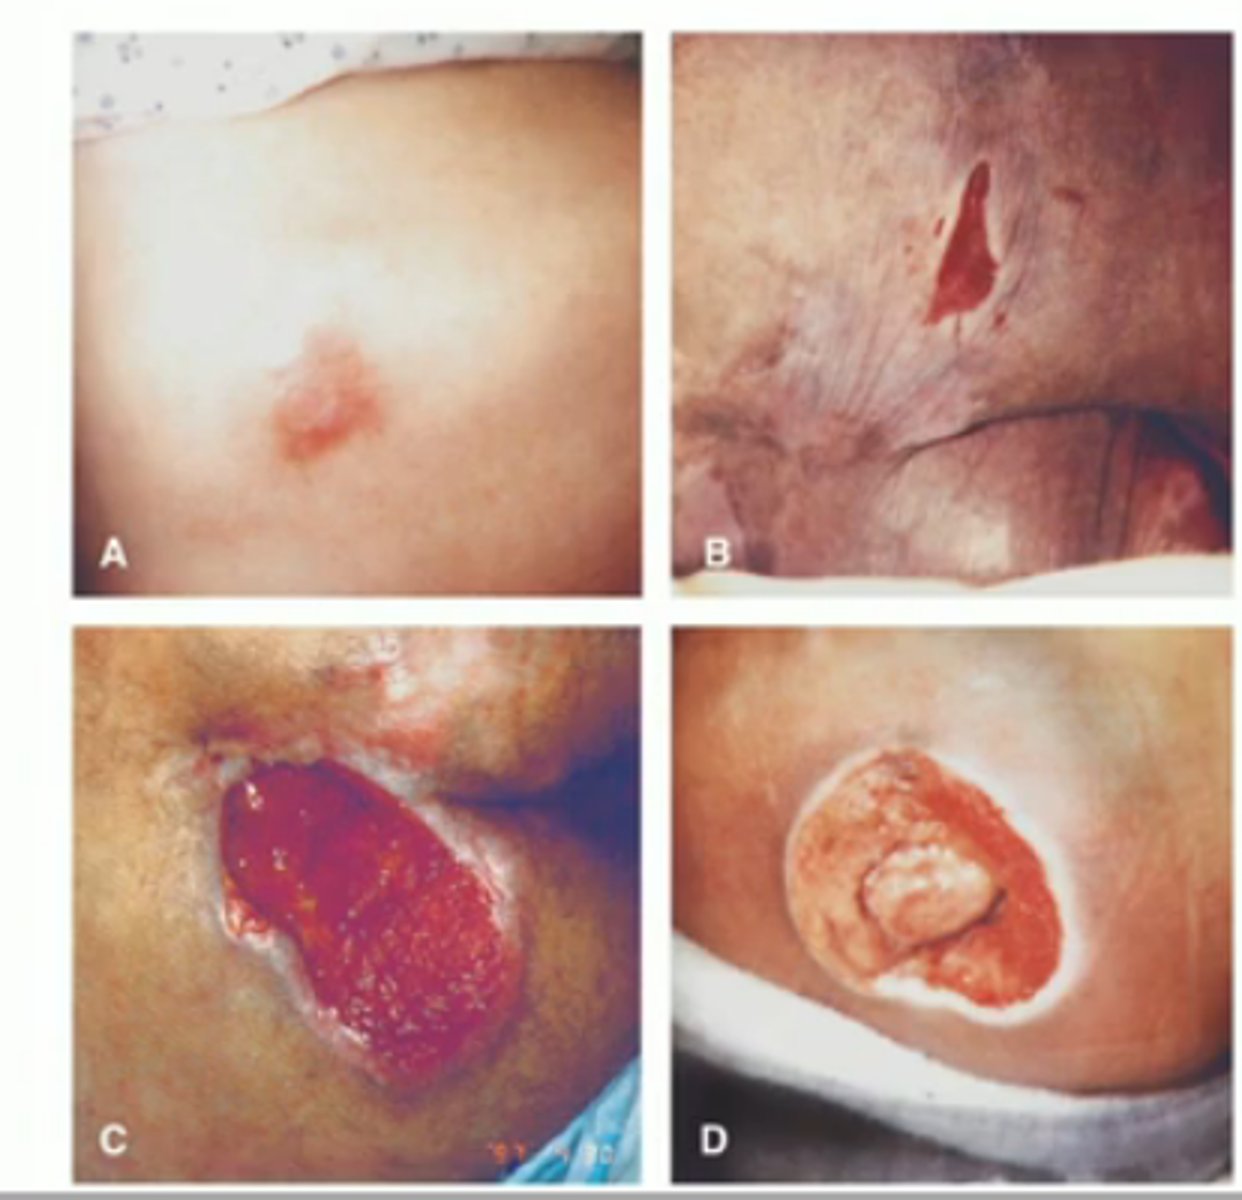

Decubitus Ulcer

skin btw hard places for too long causes compromised blood supply. Epidermis/dermis breakdown and bone can be exposed (bedsore)